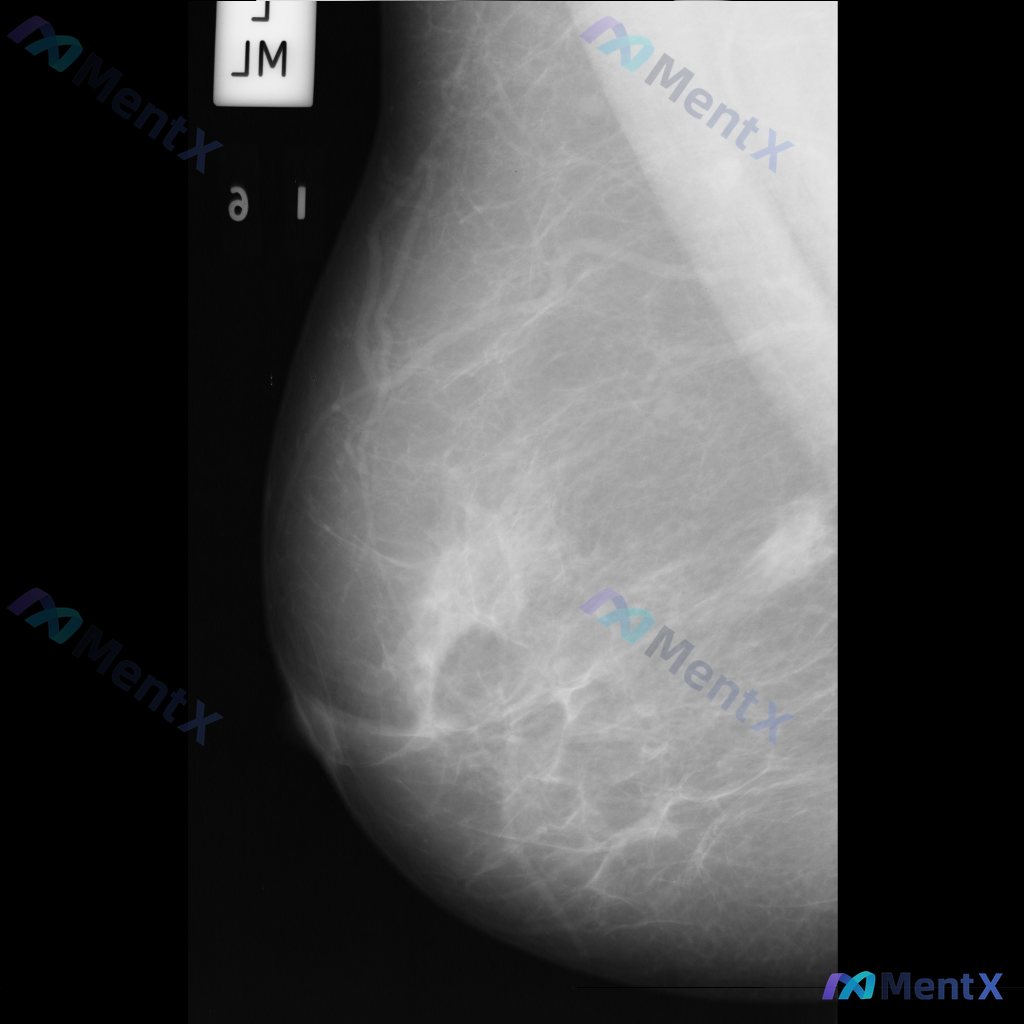

- 影像类型:左乳内外斜位(MLO位)钼靶

- 背景:乳腺呈多量腺体型(致密型),腺体组织丰富

- 主要发现:左乳下象限可见局灶性不对称密度,伴有腺体结构轻度紊乱

- 其他:目前未见明确的异常钙化、导管增粗或皮肤异常